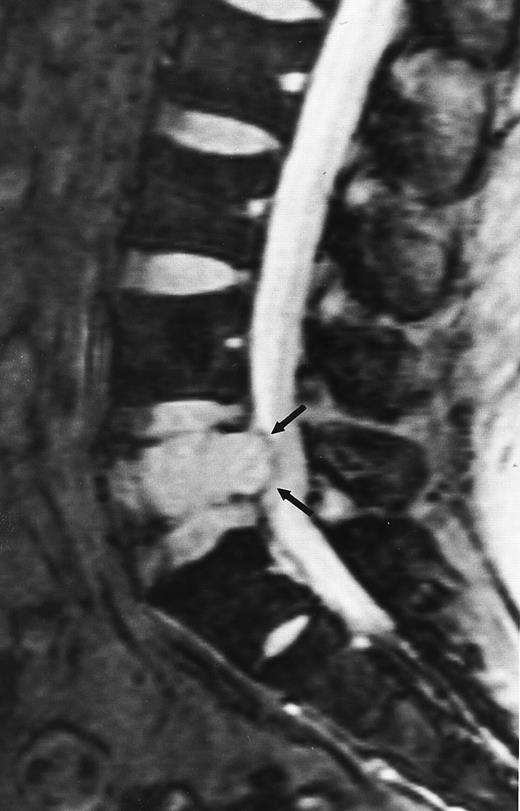

Lymphoma: multifocal bone marrow involvement. Sagittal T1-weighted (500/10, TR/TE) MR image of the lumbar spine shows multiple foci of bone marrow replacement (arrows). This appearance of lymphomatous involvement of the bone marrow is similar to bone metastases. Note extraosseous mass in the presacral space with apparent preservation of the bony cortex and small retroperitoneal lymph node at the level of L2 (arrowheads).